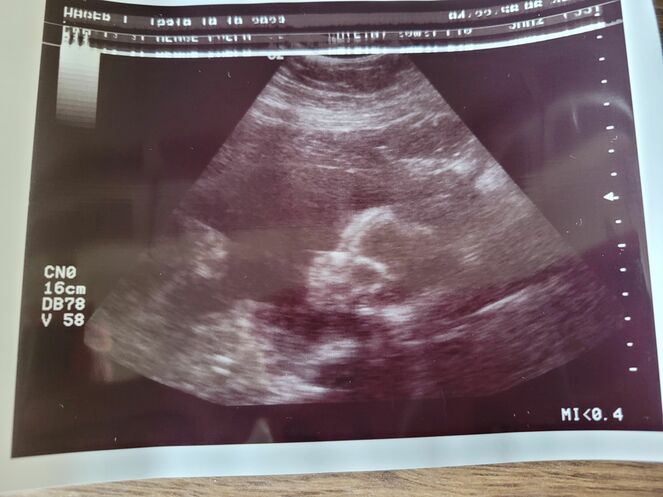

Der zweite große Ultraschall - Tagebücher aus der Schwangerschaft von Tatjana aus Nordeifel